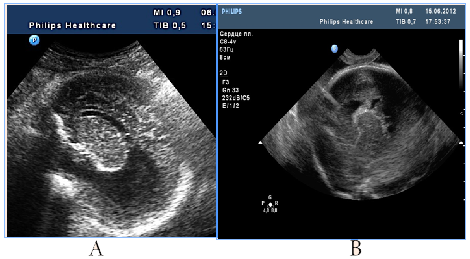

To distress associated antenatal US features of fetal brain could include signs of cortical dysplasia, antenatal intraventricular hemorrhage and PVL (Figure 9) (Figure 10). PVL in the form of small cyst was observed in two fetuses with different premorbid background one fetus with severe prenatal distress and the others with neuroinfection. Particularly attention deserved severe postnatal aftermath of fuzziness and reduced contrast of the fetal brain structures due to cerebral edema and cortical laminar necrosis at 5cases which had different pathogenetic background (Figure 10). Such contrast of structures looked like a result of wrong exposure while getting a picture, but thats were real images, with progression of edema structures looked absolutely "blurred" and cystic PVL lesions were detected. Postnatal catamnesis of all cases was extremely unfavorable.

Figure 10Fetal distress associated small-cystic PVL in the fetus and newborn.

A number of fetal intracranial changes as cortical dysplasia, intraventricular hemorrhage, PVL and reduced contrast of the fetal brain structures were observed both in infection and in severe placental dysfunction. Most of such anomalies had periventricular or subependymal localization, which could associated with universal polyetiologic pathogenetic mechanism of the germinal matrix injury. Figure 9 Antenatal distress associated sonographic brain features. A) Revers diastolic flow in the umbilical artery. B). fuzziness and reduced contrast of the fetal brain structures due to cerebral edema on the background of antenatal distress and metabolic acidosis. In clinical catamnesis perinatal loss and extremely severe persistent neurologic morbidity.

Figure 10 Fetal distress associated small-cystic PVL in the fetus and newborn. A) 31 GW, severe IGR, fetal metabolic acidosis, fuzziness and reduced contrast of the brain structures due to cerebral edema, skull deformation due to cortical necrosis, small cysts PVL in the intermediate zone (arrow). B) NSG of the newborn's brain of on the 2nd day of life, progressive small-cystic PVL. Neonatal death.